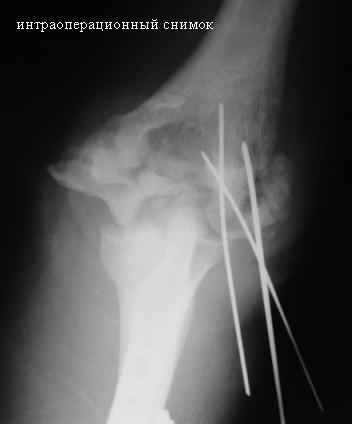

После подобного накостного остеосинтеза костей предплечья, как мне кажется, трудно ожидать консолидации, что, скорее всего повлечет за собой необходимость ревизионного остеосинтеза через 1-2 мц., в ходе которго может возникнуть вопрос о артротомии локтеовго сустава и удалении головки лучевой кости, что возможно, позволит увеличить объем движений.

Имеется ложный сустав мыщелка плечевой кости.

Необходимо выполнить остеосинтез и добится сращения и только потом возможен-артролиз локтевого сустава.

Случай интересный. Но для решения поставленных Вами вопросов необходимо ответить на несколько вопросов. Имеется ли консолидация диафизов локтевой и лучевой костей? Действительно ли имеется ложный сустав мыщелка плечевой кости? Насколько дисконгруэнтны суставные поверхности? Желательно провести спиральную компьютерную томографию с 3D реконструкцией. Если локтевая и лучевая кости сросшиеся, то на вскидку, как кажется необходимо провести стабильный погружной остеосинтез мыщелка и одновременный артролиз сустава из 2-х боковых доступов. Иммобилизация только на несколько дней для уменьшения болевого синдрома.